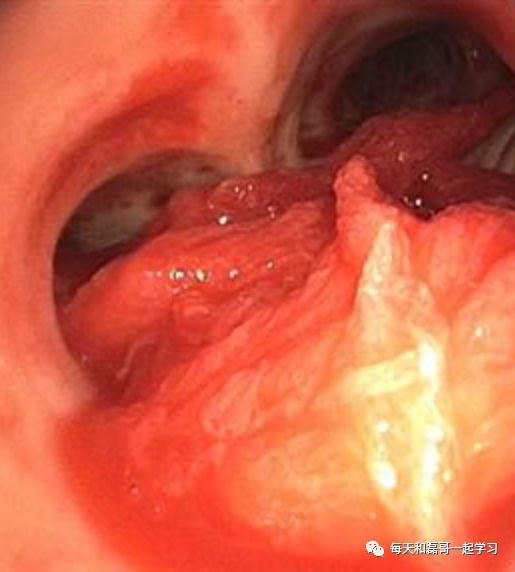

(2)大咯血或严重误吸引起的室息性呼吸衰竭

大咯血或严重误吸引起的窒息,不宜立即用呼吸机进行正压通气,因为气道被血块或误吸物阻塞,正压通气会把血块或误吸物压入小支气管而易发生肺不张,对以后的治疗和恢复不利。

首先应采取措施,将气道内的血块或误吸物清除,再进行正压通气。当然,不能一味地强调清除血块或误吸物而导致患者通气不足和缺氧,在清除误吸物的同时,应保证机体基本氧供。